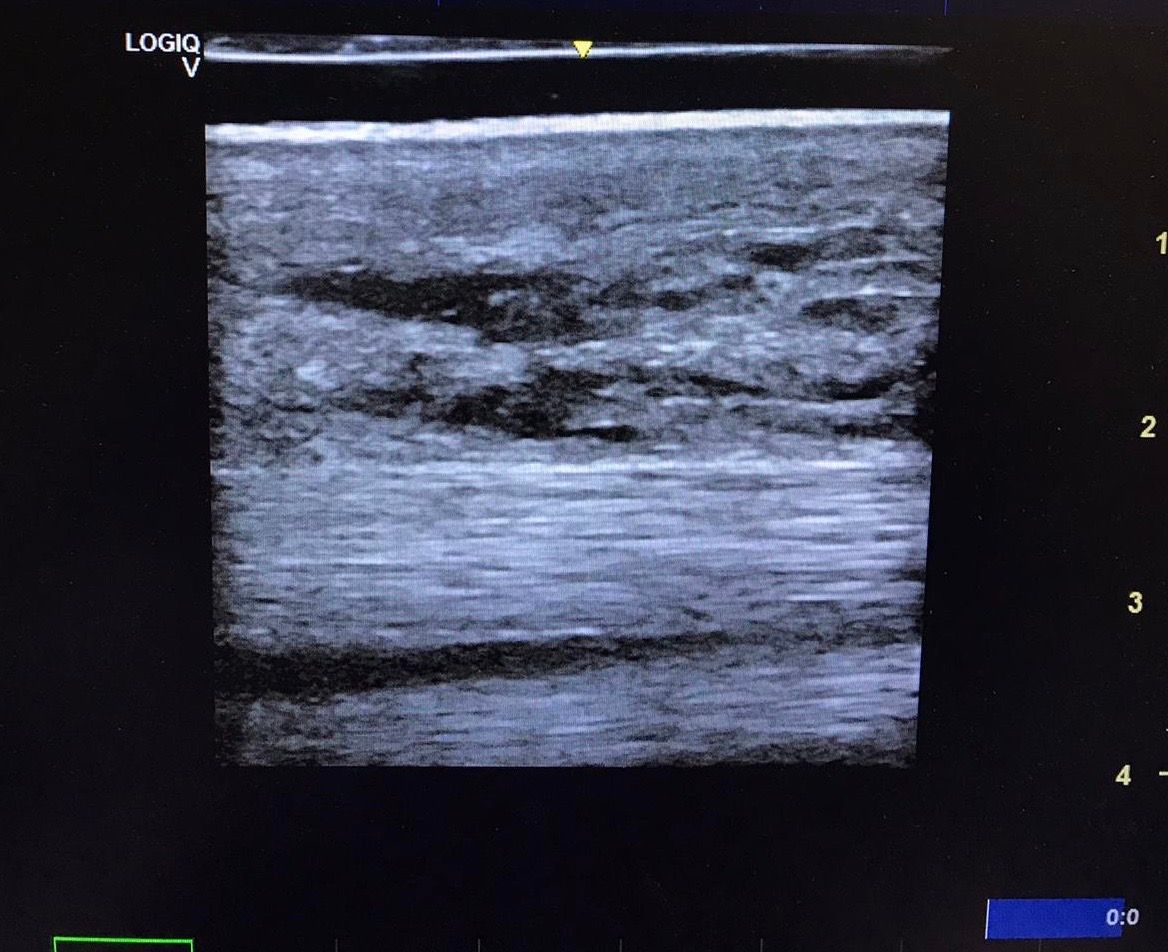

Angelehnt an das FAST-Prinzip (Focused Assessment with Sonography for Trauma) in der Notfall- und Humanmedizin, spielt Ultraschall z.B. bei Kolikern eine wichtige Rolle. Hier untersucht der Tierarzt mit einer Checkliste nach sonographischen Veränderungen im Bauchraum.

Bei Koliken nennt man dies FLASH,  fast localised abdominal sonography of horses.

Mit Hilfe eines mobilen Ultraschallgerätes lassen sich bei der Akutversorgung Ihres Pferdes mit Kolik im Stall nützliche Erkenntnisse gewinnen, die dem Tierarzt helfen die Situation zusammen mit der eingehenden klinischen Untersuchung besser einzuschätzen.

Hier hilft die FLASH-Ultraschalluntersuchung Licht ins Dunkle zu bringen, und Hinweise auf schwerwiegende Diagnosen zu stellen oder auszuschliessen. Verdachtsmomente wie Darmverlagerungen, Dünndarmschlingen und freie Flüssigkeit im Peritoneum (Bauchraum) können schnell und einfach erkannt werden. In diesen Fällen ist es oft ratsam, das augenscheinlich gesunde Pferd zur Überwachung in die nächste Pferdeklinik zu überweisen und das Zeitfenster in dem es dem Pferd noch gut geht für den Transport zu nutzen.